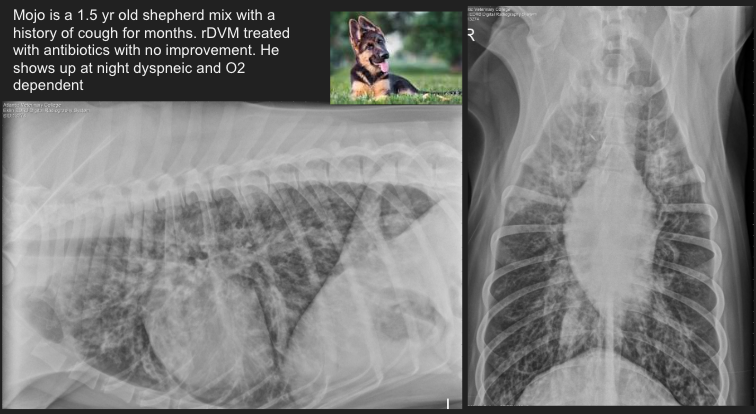

Cat. Likely condition? How do you know?

Feline asthma

flat diaphragm, donuts (bronchial pattern), huge lungs